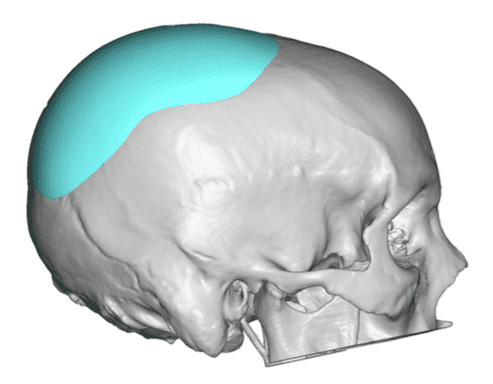

Desire for rounder shape to the top of the head from a congenital parasagittal deficiency skull shape.

Custom skull implant designed to fill in the parasagittal deficiencies.

Desire for rounder shape to the top of the head from a congenital parasagittal deficiency skull shape.

Custom skull implant designed to fill in the parasagittal deficiencies.